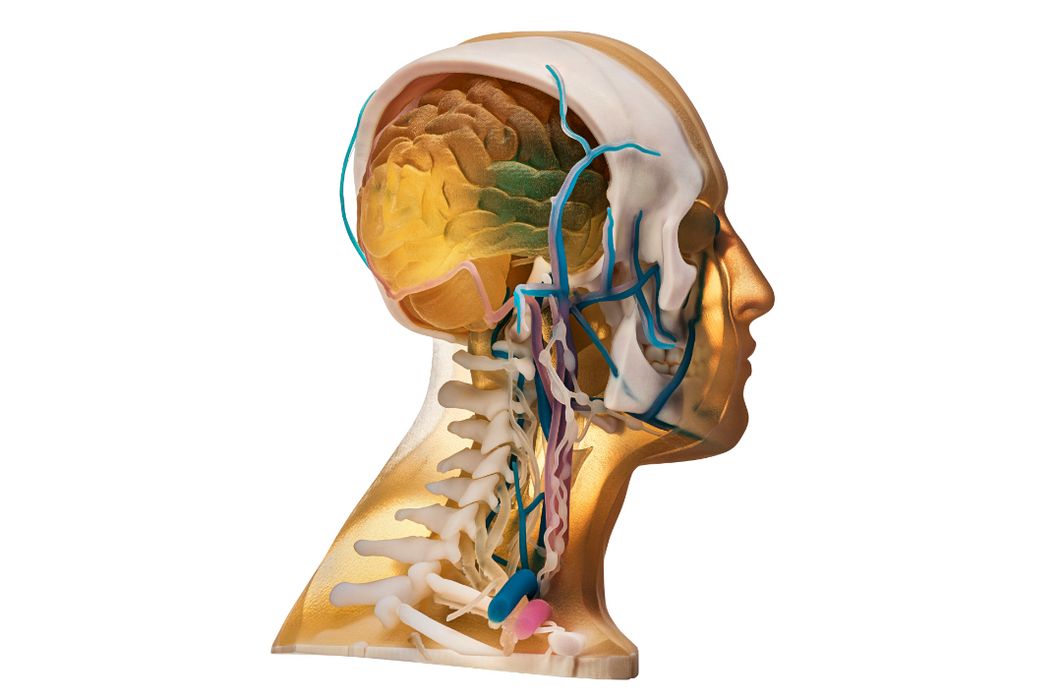

Stratasys Direct Now Offers Anatomical 3D Printing

Stratasys Direct announced new anatomical consulting and 3D printing services.